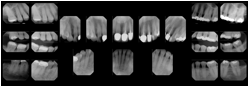

Intra-oral radiography typically involves acquisition of multiple images of various parts of the dentition. Many digital radiographic systems offer customized templates that are used for displaying the images in a study on the screen. These templates may also be referred to as mounts or view sets. The Structured Display Object represents a standard method of encoding and exchanging the layout and intended display of Structured Displays. A structured display object created in this manner could be stored with a study and exchanged with images to allow for complete reproduction of the original exam.

1. A patient visits a General Dentist where a Full Mouth Series Exam with 18 images is acquired. The dentist observes severe bone loss and refers the patient to a Periodontist. The 18 images from the Full Mouth Series along with a Structured Display are copied to a DICOM Interchange CD and sent with the patient to see the specialist. The Periodontist uses the CD to open the exam in his Dental Radiographic Software and consults via phone with the General Dentist. Both are able to observe the same exam showing the images on each user's display using the exact same layout.

Intra-oral Full Mouth Series Structured Display

Figure OO-1. Intra-oral Full Mouth Series Structured Display